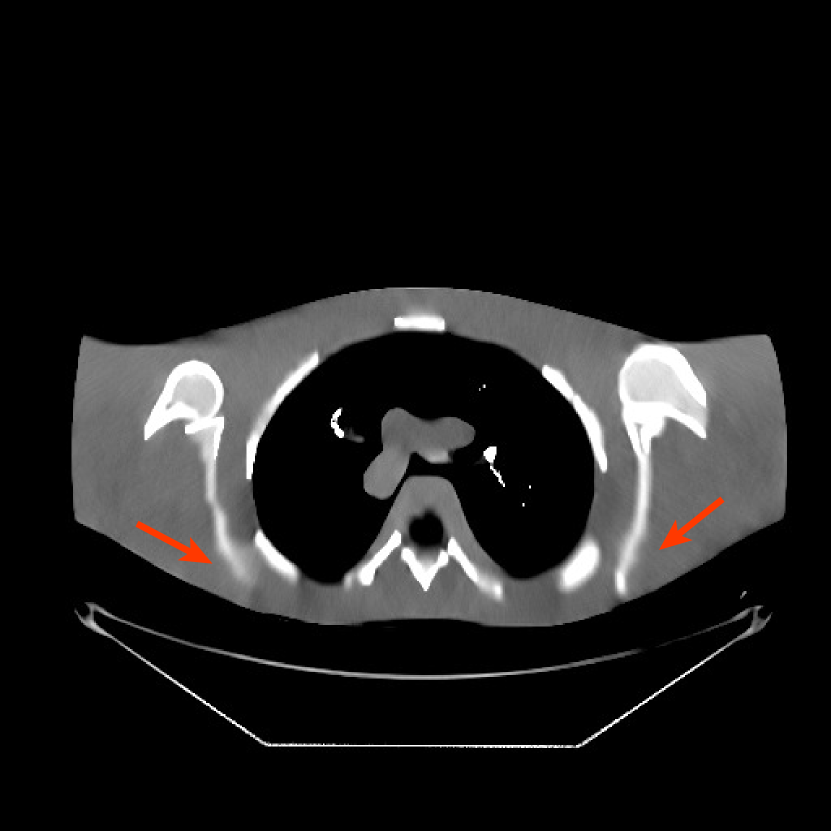

We used the pre-learned union of 15 square transforms from the XCAT phantom simulations to reconstruct the synthesized helical chest scan volume of size with mm and mm. The sinograms were of size . Since the clinical data is synthesized via the PWLS-ULTRA reconstruction, the noise model for this synthesized data is obscure, making it difficult to determine appropriate low-dose levels for such data. We tested the radiation dose of with an electronic noise variance the same as the XCAT phantom simulation, i.e., . The percentage of non-positive pre-log measurements for the synthesized clinical data in this case was around . Such non-positive values were replaced by for PWLS-based methods. Fig. 8(a) shows the “true” clinical image that was reconstructed from real clinical regular-dose sinogram using the PWLS-ULTRA method.

Similar to the XCAT phantom simulation, the initial image for both SPULTRA and PWLS-ULTRA was a reconstruction obtained using PWLS-EP. We set the regularizer parameter for PWLS-EP to to generate a smoother (with less noise) initial image, which led to good visual image equality for the SPULTRA and PWLS-ULTRA reconstructions. Since the optimization problem for PWLS-EP is strictly convex, we simply initialized PWLS-EP with a zero image. Fig. 8(b) shows the PWLS-EP reconstructed image for . We set the regularizer parameters for both PWLS-ULTRA and SPULTRA as , and .

V-B2 Reconstruction results for the synthesized clinical data

Fig. 9 shows three axial slices from the 3D reconstructions with SPULTRA and PWLS-ULTRA at : the middle slice (No. 67) and two slices located farther away from the center (No. 90 and No. 120). The image profiles along a horizontal line (shown in green) in the displayed slices are also shown in Fig. 9. The reconstructed slices using PWLS-ULTRA appear darker around the center compared to the “true” clinical image and the reconstructions with SPULTRA. This means PWLS-ULTRA produces a strong bias in the reconstruction. The bias can be observed more clearly in the profile plots: the pixel intensities for the SPULTRA reconstruction better follow those of the “true” clinical image, while those for the PWLS-ULTRA reconstruction are much worse than the “true” values. Moreover, SPULTRA achieves sharper rising and failing edges compared to PWLS-ULTRA. In other words, SPULTRA also achieves better resolution than PWLS-ULTRA. Fig. 9 also shows a zoomed-in ROI for each of the chosen slices, and highlights some small details with arrows. It is clear that in addition to reducing the bias, SPULTRA reconstructs image details better than PWLS-ULTRA.